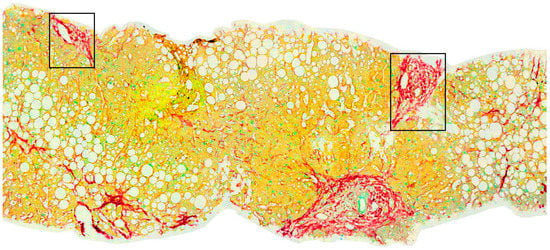

- Giannakeas, N.; Tsipouras, M.G.; Tzallas, A.T.; Kyriakidi, K.; Tsianou, Z.E.; Manousou, P.; Hall, A.; Karvounis, E.C.; Tsianos, V.; Tsianos, E. A clustering based method for collagen proportional area extraction in liver biopsy images. Proc. IEEE Eng. Med. Biol. Soc. Annu. Conf. 2015, 2015, 3097–30100. [Google Scholar] [CrossRef]

- Tsipouras, M.G.; Giannakeas, N.; Tzallas, A.T.; Tsianou, Z.E.; Manousou, P.; Hall, A.; Tsoulos, I.; Tsianos, E. A methodology for automated CPA extraction using liver biopsy image analysis and machine learning techniques. Comput. Methods Progr. Biomed. 2017, 140, 31–68. [Google Scholar] [CrossRef] [PubMed]